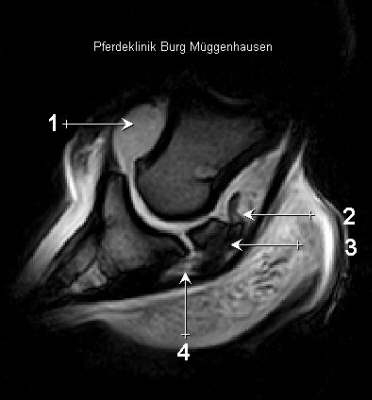

MRT Längsschnitt

1 Hochgradige Schwellung Hufgelenk, 2 Reizung des oberen Strahlbeinbandes (helles Signal im schwarzen Band), 3 hochgradige subchondrale Sklerose im Strahlbein, 4 Entzündung des unteren Srahlbeinbandes.